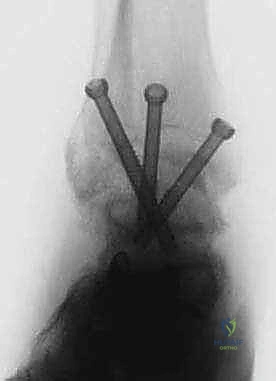

TECH FIG 3 • (continued) D. Three cannulated screws are inserted over the guide pins for definitive fixation of the arthrodesis.

TECH FIG 3 • (continued) E. Final AP and lateral radiographs confirm appropriate screw placement and position of the arthrodesis.

FIG 2 • AP and lateral postoperative radiographs are evaluated to ensure the desired alignment of the arthrodesis and check the screw position.